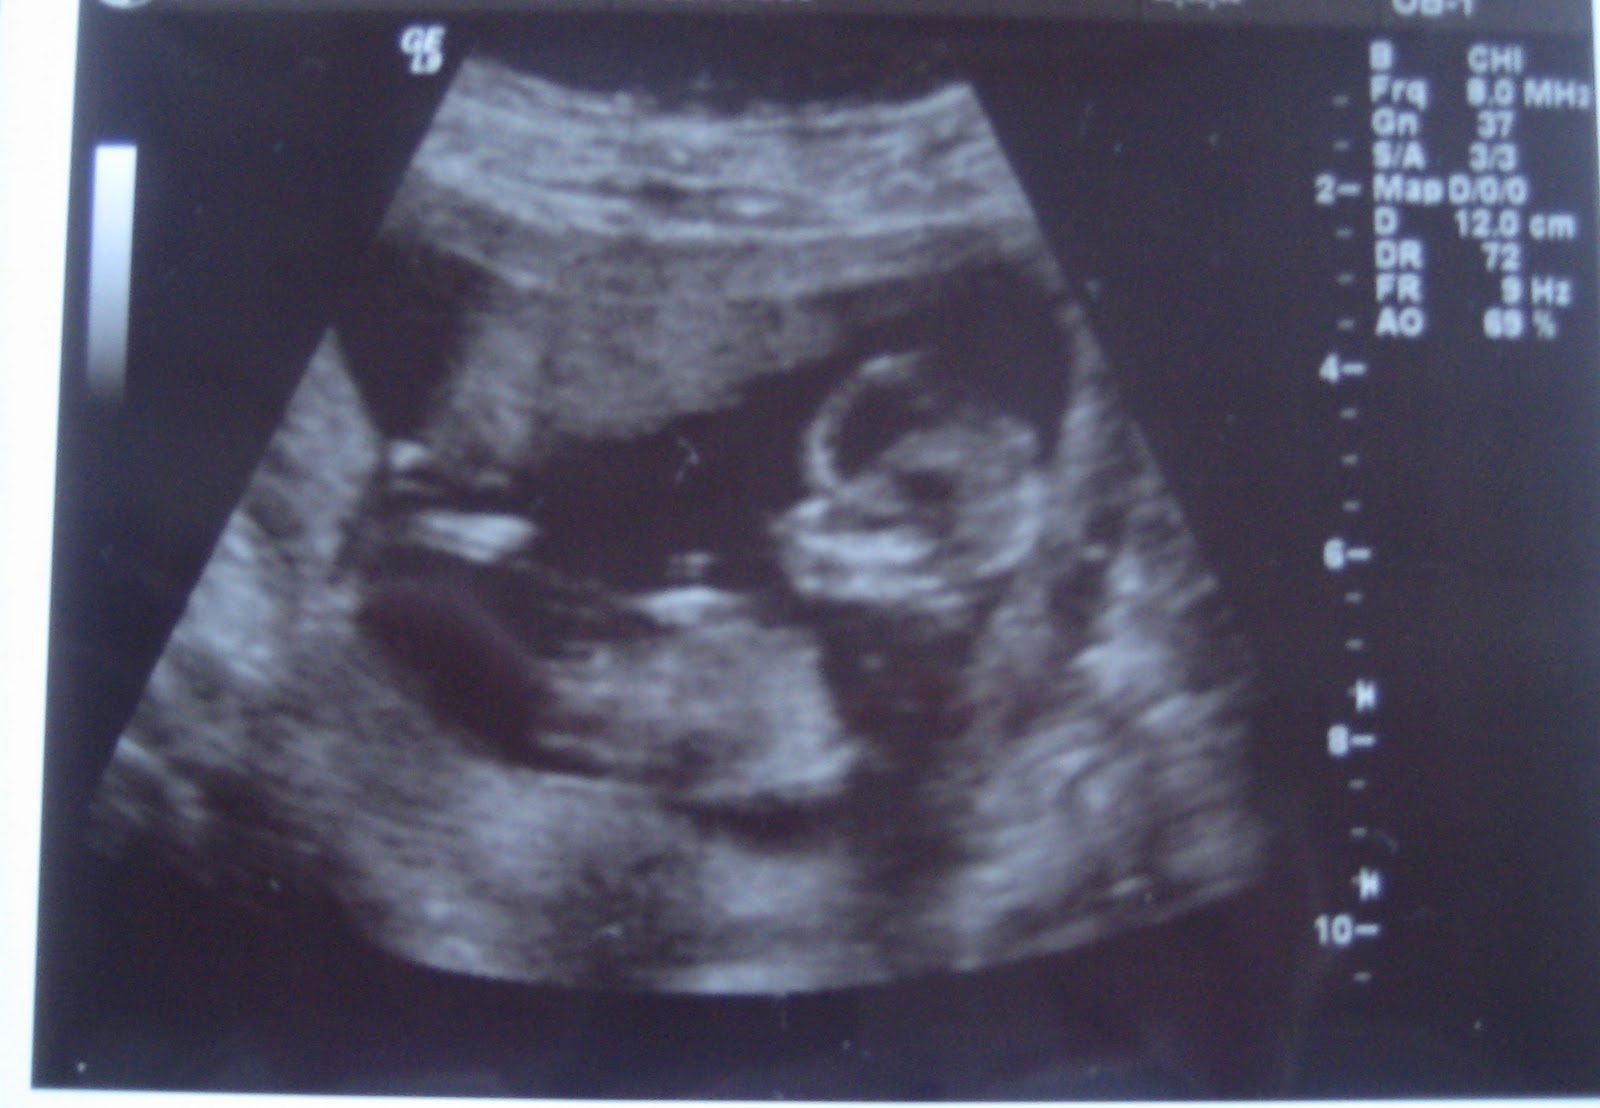

I mandags var jeg til den første scanning. Nakkefoldsscanningen.

Den bette var en rigtig sprællemand og blev ved med at vende sig, så den stakkels jordemor eller læge, ikke kunne komme til at måle nakkefolden.

Jeg blev scannet både udenpå og indeni i over en halv time inden det lykkedes. Risikoen for Mongolisme er : 1: 10500 så vi er godt tilfredse med de tal.

Den lille spire (12+5)

Spiren tæt på, med tommelfingeren i munden